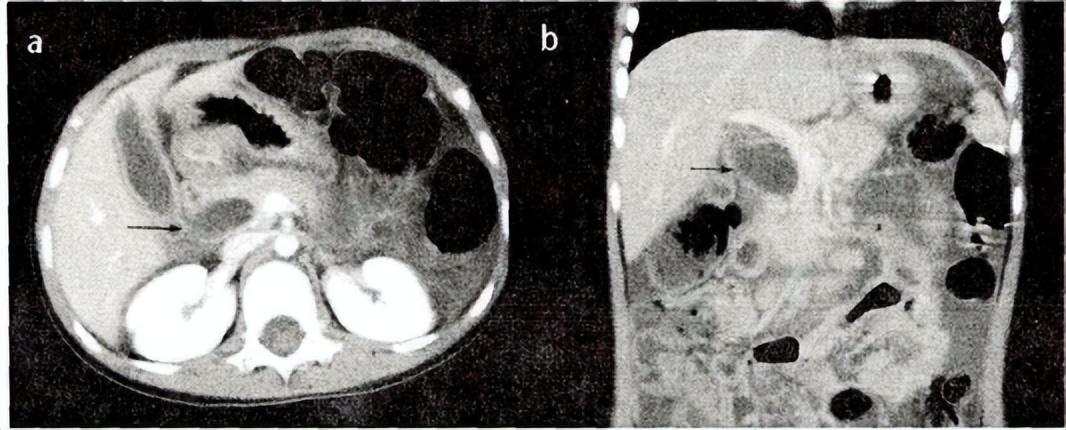

PBM患者增强CT

a.横断位原始图像;B.冠状位重建图像。一:胆总管壁明显强化,周围见游离积液